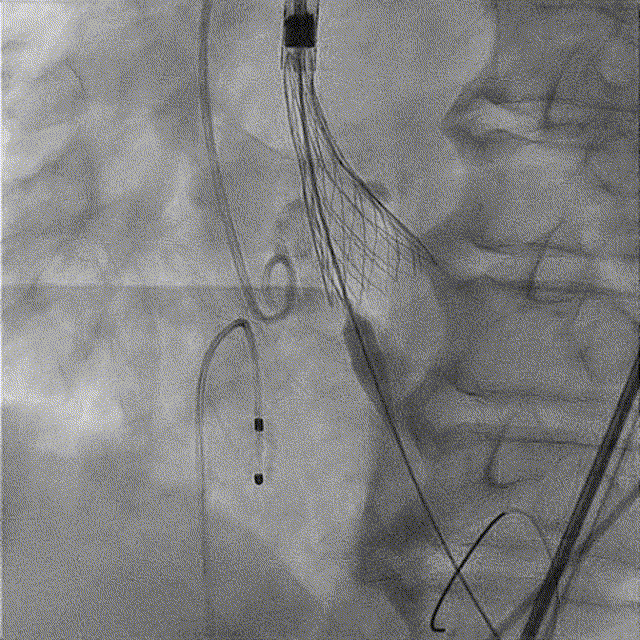

TaurusNXT植入过程

全麻后超声引导下建立入路,左侧股动脉置入TaurusNavi 20F血管鞘。跨瓣后左室放置Lunderquist导丝,使用TaurusAtlas 20mm球囊预扩,球囊无明显位移,有轻微腰征、无漏。输送系统预备同侧Snare从右股动脉送入,安全顺利通过主动脉弓。瓣膜在双窦展开位约瓣上2mm位初始定位释放,工作位造影多角度评估后予以释放(一次定位释放,未采用多次回收功能)。超声下显示瓣膜偏椭圆,之后使用TaurusAtlas 22mm球囊后扩,支架形态改善明显,导管测压由术前的70mmHg即刻下降至1mmHg,术后即刻超声心动图评估显示瓣膜位置良好,微量瓣周漏,血流动力学指标理想。

球囊预扩

预备Snare跨瓣